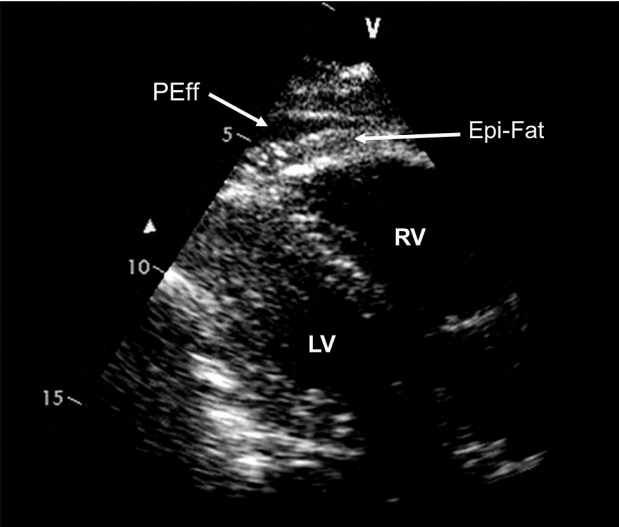

Epicardial Fat vs Pericardial Effusion

• Epicardial fat is often brighter than myocardium

• Moves in concert with heart

• Pericardial effusion is usually echolucent and motionless

ASE